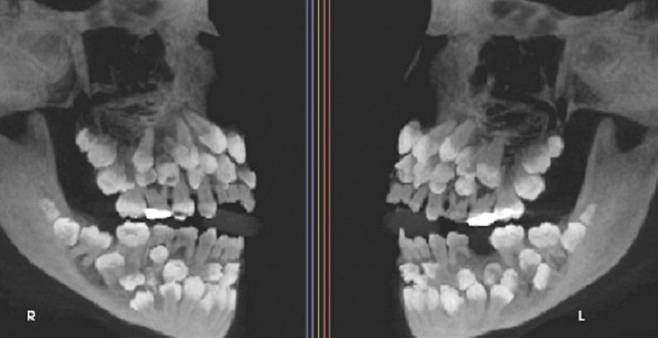

17일 VN익스프레스 등 외신에 따르면 브라질의 한 11세 소녀가 유치 1개를 발치하기 위해 병원을 찾았는데, 엑스레이 촬영 결과 소녀의 입 안에서 유치 18개·영구치 32개·과잉치 31개 등 총 81개의 치아가 발견됐다.

브라질 미나스제라이스주 주이스지포라 연방대학교 치과병원 연구팀은 "이러한 상태는 ‘다발성 과잉치증’(multiple hyperdontia)이다"라며 "보통은 1~2개의 과잉치만 발견되는 경우가 많지만, 30개가 넘는 과잉치가 확인된 사례는 전 세계적으로도 매우 드물다"고 밝혔다.